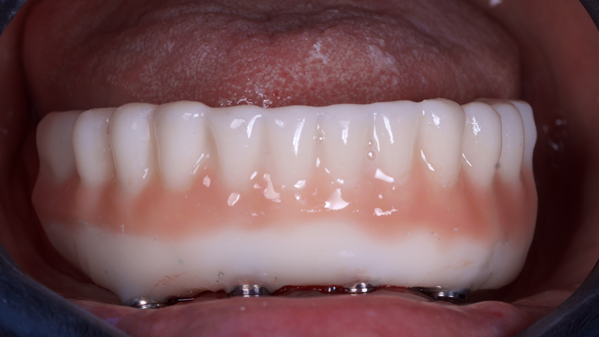

Este artigo tem como objetivo apresentar um caso clínico em que foram realizadas exodontias múltiplas, osteotomia, colocação imediata de implante e instalação de prótese híbrida de resina por impressão 3D. Todos os procedimentos foram planejados e realizados sob guia informatizado.

Este artigo demonstrou que a utilização de protótipos provisórios e cirurgia guiada podem trazer resultados satisfatórios e imediatos ao paciente, proporcionando conforto e praticidade ao consultório odontológico.